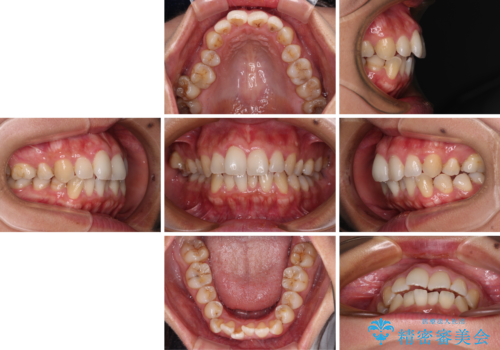

前歯のデコボコを改善 インビザラインの矯正治療

- 前歯のデコボコを治したいとのことで来院された患者様です。

上下顎ともに歯列全体の後方移動とIPR(歯と歯の間を削る)によってデコボコが解消するように設計し、インビザラインにより治療を行うこととしました。